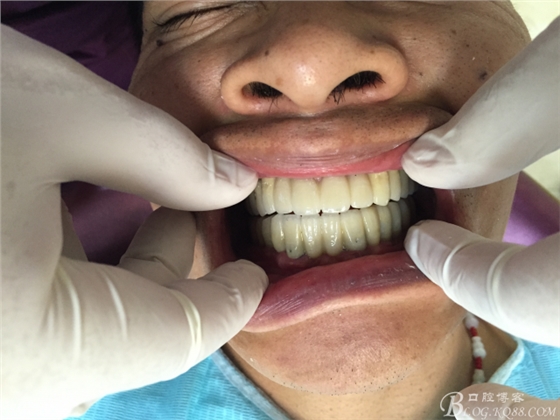

患者37歲 男 全口牙周病 手術(shù)一次完成 全程3小時(shí)全口種植修復(fù)全口種植修復(fù)全口種植修復(fù)全口種植修復(fù)全口種植修復(fù)全口種植修復(fù)全口種植修復(fù)全口種植修復(fù)全口種植修復(fù)全口種植修復(fù)全口種植修復(fù)全口種植修復(fù)全口種植修復(fù)全口種植修復(fù)全口種植修復(fù)